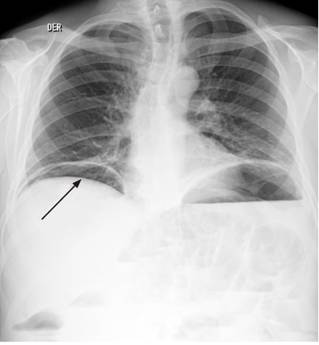

Se inició el manejo con líquidos intravenosos (y se logró normalidad hemodinámica) y cubrimiento antibiótico a base de ampicilina/sulbactam. Se solicitaron estudios paraclínicos que mostraron un hemograma con leucocitos: 15 530/μL, hemoglobina: 10,4 g/dL y plaquetas: 130 000/μL, además de proteína C-reactiva (PCR): 114 mg/dL, gases arteriales con pH: 7,31, presión parcial de dióxido de carbono (pCO2): 22,7 mm Hg, presión parcial de oxígeno (PO2): 70,3 mm Hg, bicarbonato (HCO3): 11,2 mmol/L y base exceso (BE): -12,7 mmol/L. Se realizaron radiografías de tórax de pie (Figura 1) y de abdomen simple (Figura 2).

Se presenta el caso de un adulto mayor, quien consultó por dolor abdominal agudo de características descritas, asociado con manifestaciones psiquiátricas compatibles con delirio. Clínicamente se encontraron datos de síndrome de respuesta inflamatoria sistémica (SIRS) con un qSOFA positivo >2 10. Se tomaron estudios paraclínicos que reportaron reactantes inflamatorios altos y hemograma con desviación a la izquierda en el paciente con acidosis metabólica, lo que apoyó el diagnóstico de sepsis 10 y ameritó una intervención guiada por metas. Durante la observación se evidenció por imágenes la ruptura de una víscera hueca y signos de obstrucción intestinal parcial 12. Por la localización anatómica del dolor se sospechó patología apendicular; sin embargo, no se descartó la posibilidad de perforación espontánea del intestino delgado. Las causas de perforación espontánea del intestino delgado aparecen en la Tabla 1.